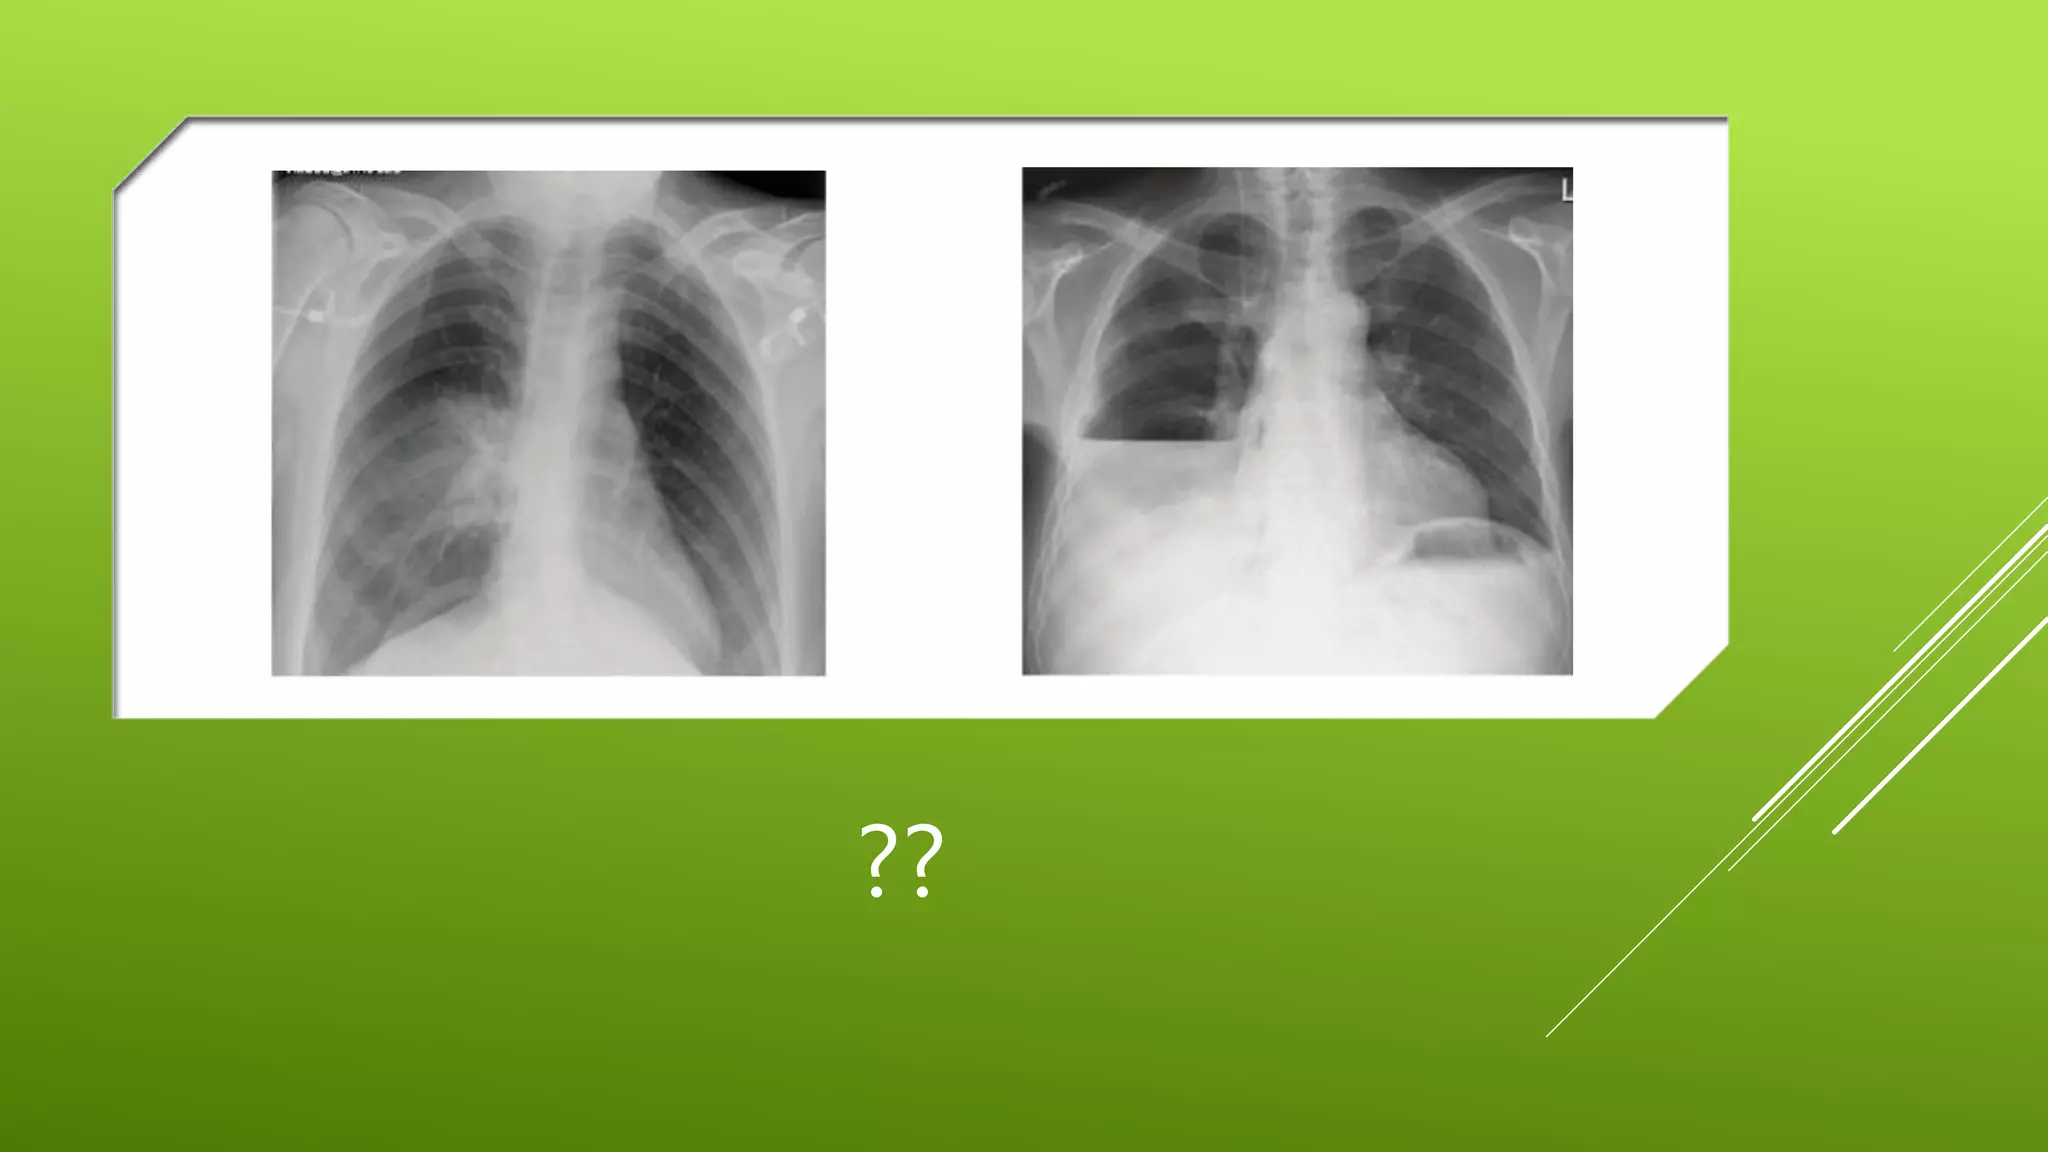

This document contains a series of radiology-related questions and prompts seeking identification and interpretation of various imaging findings, patient presentation details, monitoring values, scoring systems, diagnoses, and management steps. Specific topics include identifying x-ray and CT scan findings, interpreting EKG results, recognizing arrhythmias, assessing intubated and post-surgery patients, and evaluating compliance with treatment plans.